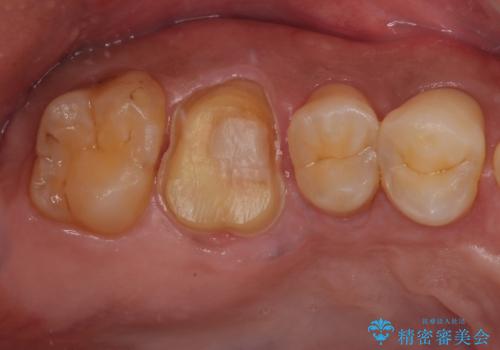

- セラミックの詰め物が割れたとのことで来院された患者様です。現在に至るまで二度セラミックの詰めもの(セラミックインレー)が割れていて、噛み合わせも強い方なのでフルジルコニアクラウンとゴールドクラウン(PGAクラウン)を治療方法としてご提案しました。

患者様と相談した結果、強度と見た目の良いフルジルコニアクラウンで治療していくことになりました。

拡大鏡視野下で保険のプラスチック(コンポジットレジン)、虫歯を除去し、フルジルコニアクラウン、に適した形にしました。